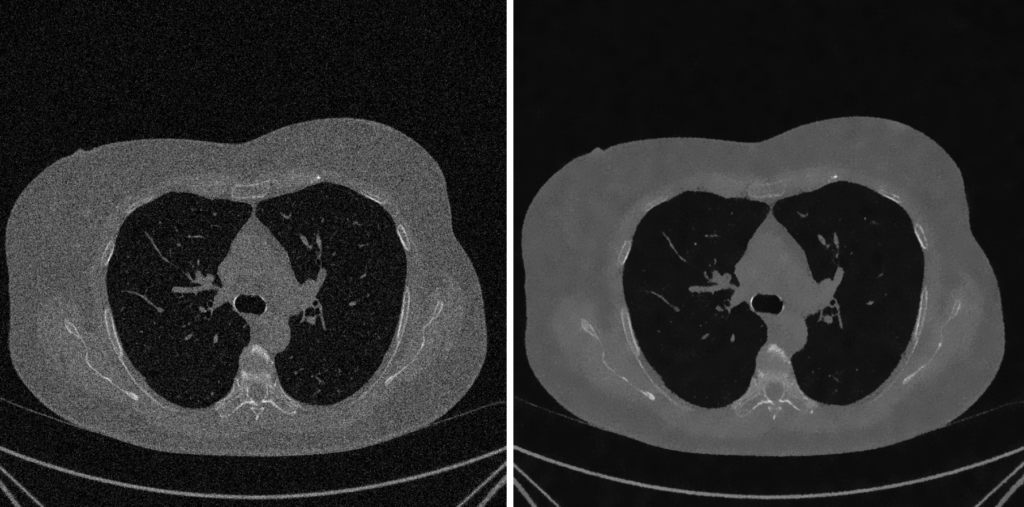

5. Fase 4: Miglioramento Visivo e Contrasto

Un’immagine quantitativamente ineccepibile (ad esempio, un’immagine a 16 bit, CV_16U), dopo le correzioni e i filtraggi, può risultare visivamente “piatta” o troppo scura. Questo fenomeno si verifica quando i dati rilevanti sono concentrati in un intervallo ristretto di livelli di grigio.

E’ allora necessario effettuare un’operazione di “stiramento” dell’istogramma. L’obiettivo è estendere la distribuzione dei pixel per sfruttare appieno la gamma dinamica disponibile sul dispositivo di visualizzazione (ad esempio, da 0 a 255).

Equalizzazione Globale dell’Istogramma (Histogram Equalization – HE)

Questo metodo tradizionale agisce sull’intera immagine per rimappare e ridistribuire le intensità dei pixel in modo uniforme.

- Funzionamento: La tecnica mira a trasformare l’istogramma dell’immagine rendendolo il più uniforme (piatto) possibile. Il principio è che una distribuzione equa di tutti i livelli di grigio massimizza il contrasto complessivo.

- Svantaggi: Essendo un’operazione che considera l’immagine nel suo complesso, aree ampie e poco variegate (come uno sfondo omogeneo) tendono a dominare l’istogramma. Questo può portare a “schiacciare” i dettagli presenti in regioni più piccole e, potenzialmente, ad amplificare notevolmente il rumore di fondo.

Equalizzazione Adattativa dell’Istogramma (CLAHE)

CLAHE rappresenta la soluzione “intelligente” e all’avanguardia per superare i limiti dell’equalizzazione globale, affermandosi come lo standard de-facto nell’imaging medicale.

Principio Fondamentale

A differenza dei metodi che analizzano l’istogramma complessivo, CLAHE opera localmente. Migliora il contrasto solo nelle aree necessarie, evitando al contempo l’amplificazione del rumore di fondo.

Processo Operativo (I 5 Passaggi)

- Suddivisione in Tessere (Tile Generation): L’immagine viene inizialmente suddivisa in una griglia di blocchi regionali di piccole dimensioni (le “tessere,” ad esempio 8×8).

- Calcolo degli Istogrammi Locali: Per ciascuna tessera viene calcolato un istogramma indipendente.

- Clipping dell’Istogramma (Il “CL” di CLAHE): Questa fase cruciale impone un “limite” (il Clip Limit). Qualsiasi livello di grigio (bin) che superi tale limite, spesso a causa della presenza di rumore, viene “tagliato.” L’eccesso risultante viene poi ridistribuito uniformemente sugli altri bin. Questo meccanismo previene efficacemente la sovra-amplificazione del rumore.

- Equalizzazione Adattiva: Viene applicata la classica equalizzazione (basata sulla funzione di distribuzione cumulativa – CDF) a ciascun istogramma locale che è stato “clippato.”

- Interpolazione per Fluidità: Per eliminare l’effetto visivo “a scacchiera” derivante dalla divisione in tessere, i valori finali dei pixel vengono calcolati tramite interpolazione bilineare tra le mappature delle tessere adiacenti, garantendo una transizione cromatica fluida e omogenea.